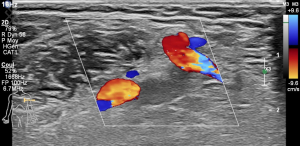

Doppler Veineux des Membres supérieurs